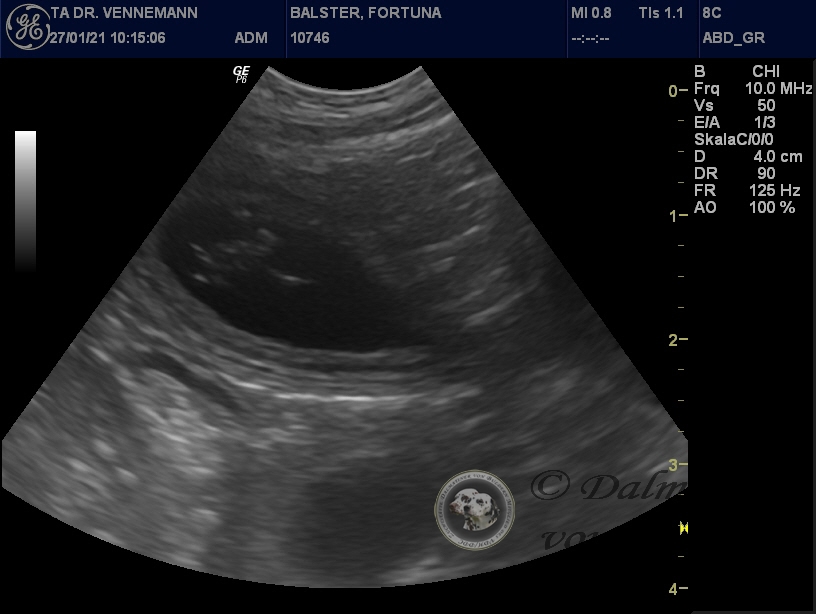

28.01.2021

Da sind sie nun...

...die ersten Bilder unserer kleinen Q-chen!

Der Ultraschall beim Tierarzt unseres Vertrauens hat uns Einblick in Selmas Bäuchlein gegeben. Deutlich sichtbar waren die schlagenden Herzchen der Winzlinge zu erkennen - immer wieder ein wunderbarer Anblick!